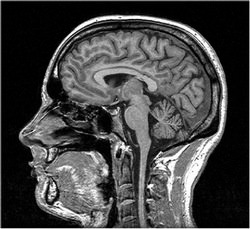

Scientists from the Max Planck Institute of Psychiatry in Munich, the Charité hospital in Berlin, and the Max Planck Institute for Human Cognitive and Brain Sciences teamed up with a handful of lucid dreamers and an MRI machine.

At the same time, functional magnetic resonance imaging scans enabled the researchers to gain a live view on what goes on in the brain during this lucid action.

Interestingly, the same areas of the brain were also active when the lucid dreamers clenched their fists in real life - or even simply imagined doing so.